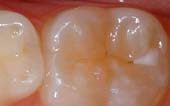

Seal Out Decay

A sealant is a protective coating that is applied to the chewing surfaces (grooves) of the back teeth (premolars and molars), where four out of five cavities in children are found. This sealant acts as a barrier to food, plaque and acid, thus protecting the decay-prone areas of the teeth.

Tooth before sealant applied - Pediatric Dentist in Keller, Fort Worth and Southlake, TX - Bridget McAnthony, DDS

Before Sealant Applied

Tooth after sealant applied - Pediatric Dentist in Keller, Fort Worth and Southlake, TX - Bridget McAnthony, DDS

After Sealant Applied